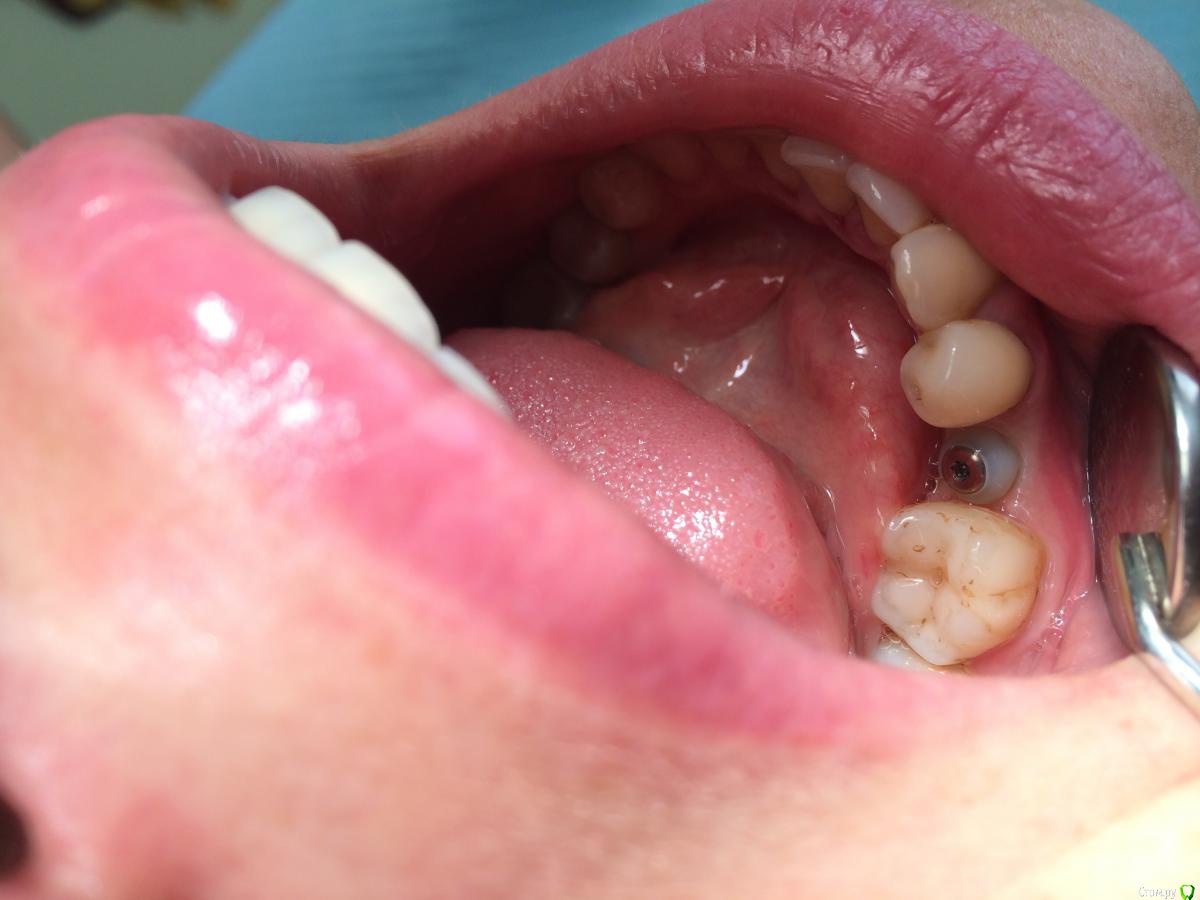

Кариес+ Опубликовано 29 августа, 2016 Автор Поделиться Опубликовано 29 августа, 2016 Картина спустя месяц, пока все стабильно, немного индивидуализировал формик. Кажись десны немного маловато. Каким методом лучше провести пластику , конверт? Ссылка на комментарий

Кариес+ Опубликовано 29 августа, 2016 Автор Поделиться Опубликовано 29 августа, 2016 (изменено) По высоте было миллиметра 3 Изменено 29 августа, 2016 пользователем Кариес+ Ссылка на комментарий

Fibez Опубликовано 29 августа, 2016 Поделиться Опубликовано 29 августа, 2016 десны достаточно 2 Ссылка на комментарий

red_butler Опубликовано 29 августа, 2016 Поделиться Опубликовано 29 августа, 2016 десны достаточно+ 1 Ссылка на комментарий